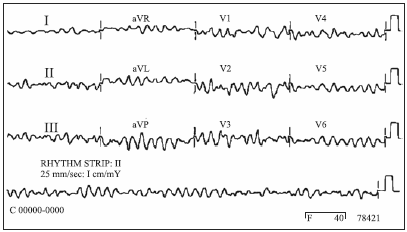

Enquanto eram tomadas as medidas iniciais, o paciente apresentou rebaixamento do nível de consciência, tornando-se arresponsivo. O aparelho de eletrocardiograma ainda se encontrava conectado ao paciente e foi realizado o registro a seguir.

A conduta que deve ser prontamente adotada é: